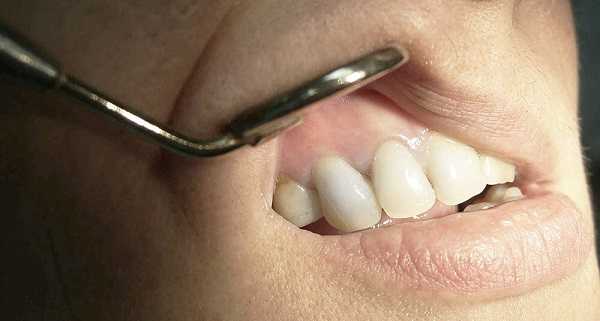

При осмотре врач-стоматолог выявляет потемнение цвета зуба (пораженный зуб может быть под коронкой, в таком случае она значительно светлее, чем сам зуб) или запущенный кариозный процесс. Зондирование корневых каналов при этом безболезненно и сопровождается выделением желтоватой жидкости. Перкуссия, как правило, редко вызывает какие-либо дискомфортные ощущения. Для уточнения диагноза проводится: